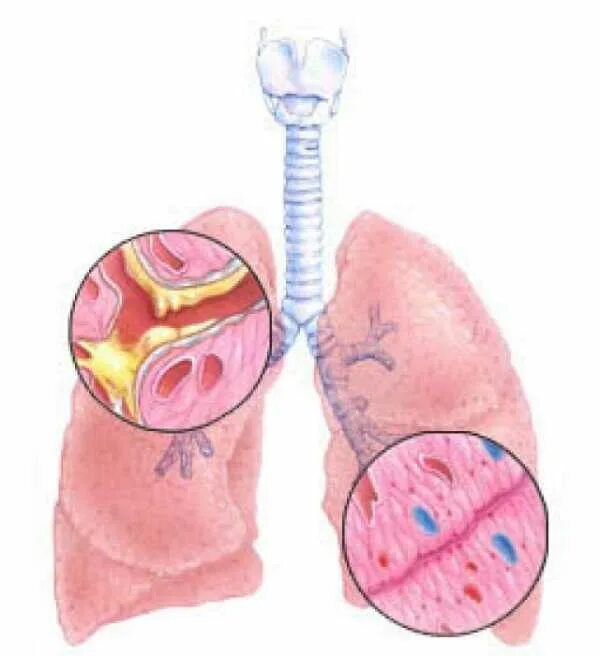

Диффузный эндобронхит